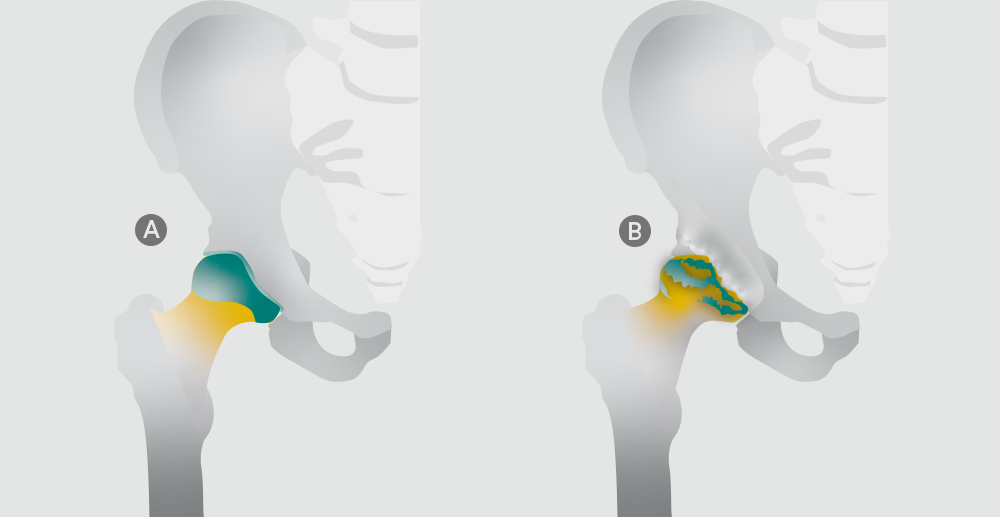

Das Hüftgelenk verbindet das Becken mit dem Oberschenkel. Hier sitzt der Oberschenkelkopf (Hüftkopf) in der Hüftpfanne. Das Hüftgelenk ist ein sogenanntes Kugelgelenk: deshalb ist es möglich, dass Sie Ihr Bein in alle Richtungen bewegen und drehen können. In einem gesunden Hüftgelenk sind sowohl der Hüftkopf des Oberschenkelknochens als auch die Gelenkpfanne des Beckenknochens mit Knorpel überzogen (Abbildung A).

Bei einer Hüftgelenksarthrose (Coxarthrose) verschleißt die schützende Knorpelschicht der Knochen im Hüftgelenk, wird rissig und dünner (Abbildung B). Dadurch steigt die Druckbelastung der Knochen. Mit der Zeit lässt die Beweglichkeit des Gelenks immer weiter nach. Mediziner verwenden dafür oft den Begriff Degeneration. Umgangssprachlich wird Arthrose auch Gelenkverschleiß genannt.